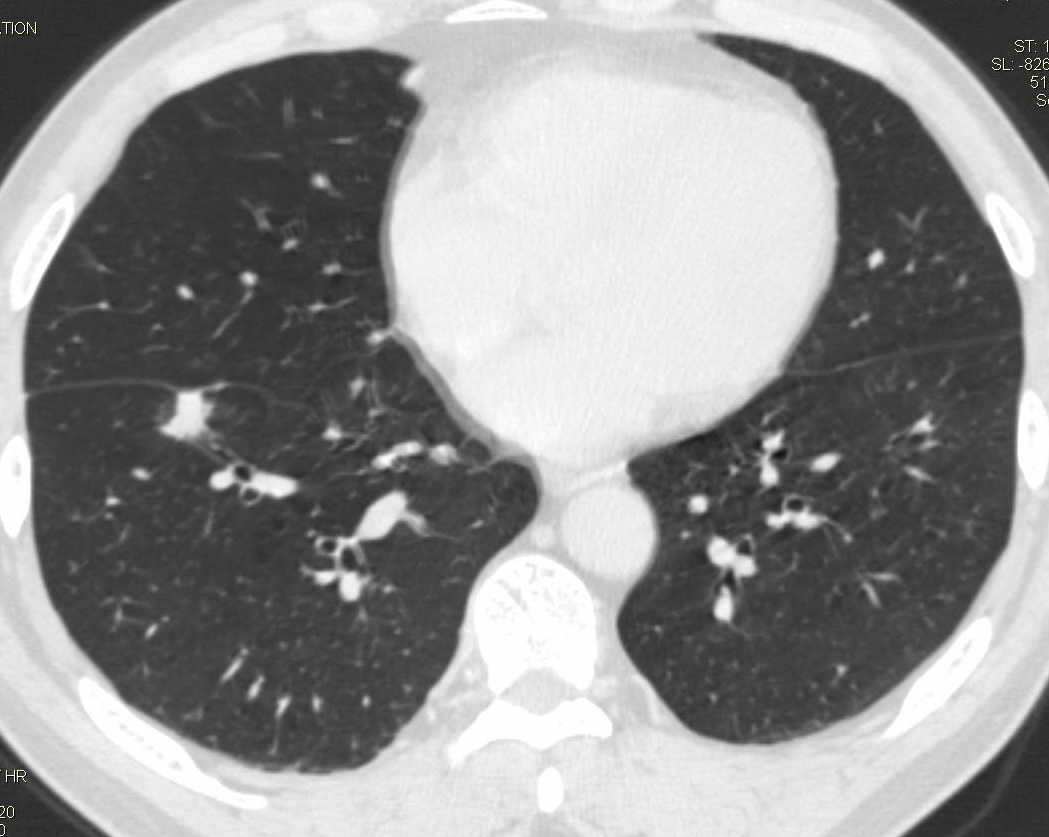

标题: CT15857:男性 58岁 咳痰带血 无发热 请各位大侠发表一下意见 [打印本页]

标题: CT15857:男性 58岁 咳痰带血 无发热 请各位大侠发表一下意见

两肺下叶肺纹理增多、增粗并呈“树芽状”改变。支气管扩张呈囊状,部分呈柱状改变。其周围可见散在的斑片样及条索样密度增高影,右肺下叶近叶间胸膜可见一形态不规则的高密度结节影,并与胸膜粘连。

考虑:支扩并发感染。

双肺多发炎性病灶,结核可能性大,建议抗炎治疗复查.右肺下叶前基底段结节灶,高度警惕肺癌可能

双肺间质性改变(间质纤维化?)伴支扩。右肺下叶有毛刺的小结节,考虑周围型肺癌可能性。